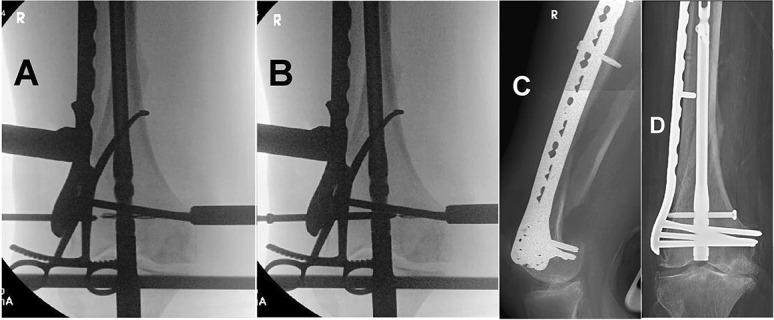

The use of nail-plate constructs has been suggested for treatment of elderly patients with distal femur fractures to facilitate stable fixation and early ambulation. In this article, we describe a technique to link the 2 implants without the use of fluoroscopic "perfect-circle" technique. This technique can be used with implants from different manufacturers.

有人建议使用钉板结构治疗老年股骨远端骨折,以促进稳定固定和早期活动。在本文中,我们描述了一种不使用透视“完美圆圈”技术连接两种植入物的技术。该技术可用于不同制造商生产的植入物。